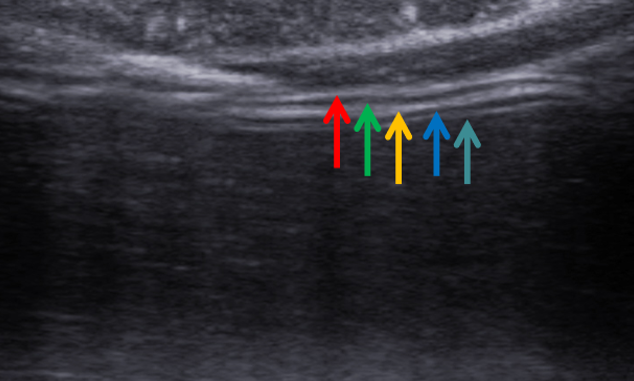

胃壁三强二弱结构(大弯)